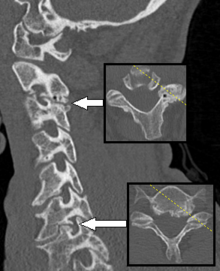

CT scan of a man presenting with radiculopathy of the left cervical spinal nerve 7. It shows spondylosis with osteophytes between the vertebral bodies C6 and C7 on the left side, causing foraminal stenosis at this level (lower arrow, also showing axial plane), explaining the symptoms. There is also spondylosis of the facet joint between C2 and C3, with some foraminal stenosis at this level (upper arrow), which appears to be asymptomatic.